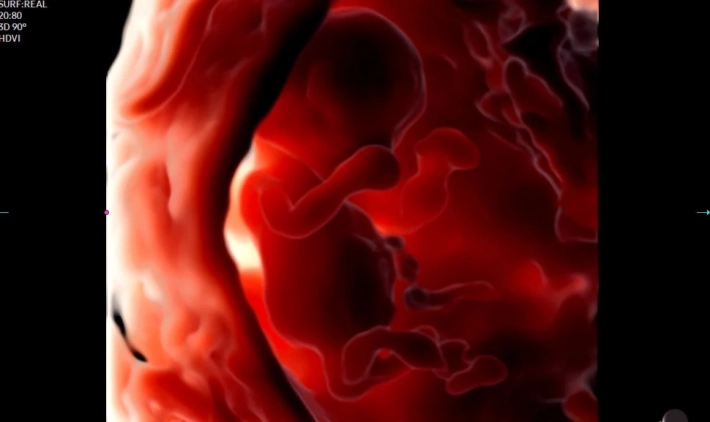

PortraitVue™ — эмоции в реальном времени

Уникальная технология PortraitVue™ позволяет реконструировать лицо плода по 3D-изображению, восстанавливая естественные черты. Это не только точная диагностика, но и незабываемый опыт для будущих родителей.